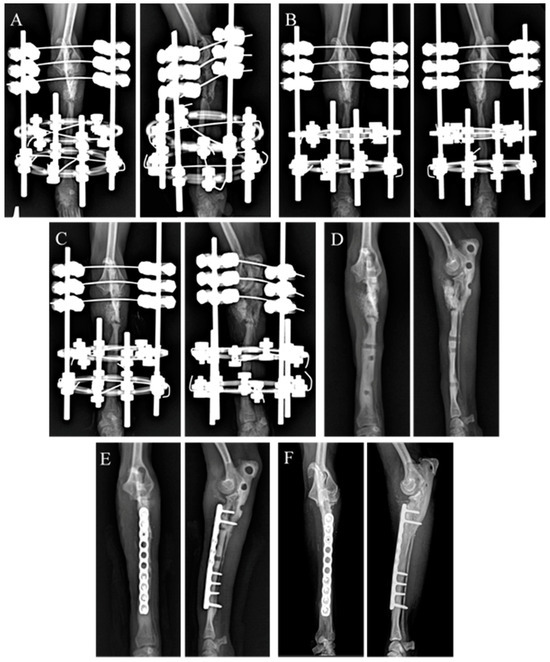

The gait analysis after the second surgery was objectively evaluated using a pressure sensor walkway (Walkway, Tekscan Inc., Norwood, MA, USA), and the symmetry index (SI) and weight distribution (WD) were assessed using the data obtained from Tekscan software (Walkway 7.66). The gait analysis results at 12 days, 5 weeks, and 4.8 years post second surgery revealed a reduction in the difference between the peak vertical force (PVF) and vertical impulse (VI) for both forelimbs (Figure 7). Compared with pre-operative values, the SI and WD analysis showed an increase in both PVF and VI in the affected limb (one-way RM ANOVA, p < 0.0001). Additionally, the SI-PVF value became negative, indicating an increase in the PVF of the left limb compared with that of the right limb. This suggests an improvement in walking ability at 4.8 years post second surgery.

Recently, gait analysis has been increasingly applied to objectively detect and monitor lameness in small animals with musculoskeletal or neurological disorders [39,40]. In this case, kinetic gait analysis based on paw pressure was used to assess postoperative gait. At 12 and 5 weeks after the second surgery (Figure 7), the differences in the PVF and VI between the affected and normal limbs tended to decrease, approaching an SI of zero. At 4.8 years, distinctive gait characteristics of the shorter left limb were observed, including increased vertical displacement of the center of mass and decreased stance time, stride length, and walking speed [35]. The patient also exhibited these characteristics in the shorter left forelimb, resulting in an increased PVF and decreased VI. Consequently, the SI-PVF value becomes negative, whereas the SI-VI value remains positive. At 4.8 years, the absolute mean values of SI-PVF and SI-VI were 3.53% and 11.64%, respectively. Even in healthy dogs, there can be a maximum of <6% asymmetry between limbs [41]. The SI generally records the differences between normal and pathological gaits and evaluates changes in asymmetry due to enhanced pathological conditions [42]. Although the SI-VI value was relatively more asymmetric, owing to the reduced stance time of the left limb compared to that of the normal limb, the SI-PVF fell within the range of asymmetry observed in normal dogs.

Figure 7. Gait analysis of the pressure sensor walkway. (A,B) The symmetry index of the left forelimb decreased after fixation of the radius locking plate (2nd Surgery). (C,D) Weight distribution of the bilateral limbs revealed a tendency towards restoration of the left forelimb function. PVF: peak vertical force; VI: vertical impulse; RF: right forelimb; LF: left forelimb; * significant change from pre-operation; significant change from 12 days after fixation of radius locking plate.